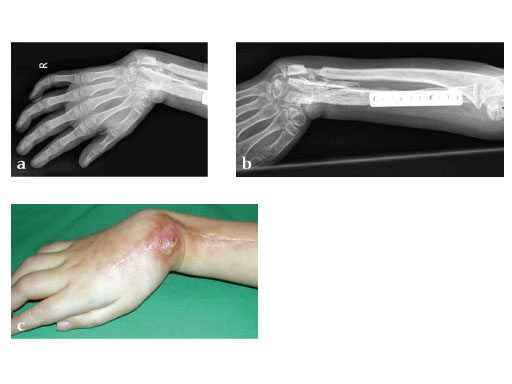

Fig 2ab: Resection of necrotic radius, temporary ExFix and pallacos spacer.